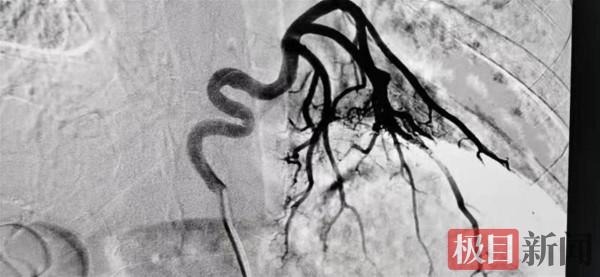

12月1日,孫先生做完運動後突然感覺胸口難受,接著大口吐鮮血。家人嚇壞了,趕緊送他到了武漢市肺科醫院。當CT增強掃描結果顯現時,在場醫生都驚呆了:只見一根手指粗的血管,從他的腹主動脈一路蜿蜒,抵達他的肺部後散成多個分支,如同生根一般深入到他的左肺基底。

該院放射科醫生李晟說,這是極為罕見的“異常體動脈供應正常左下肺基底段”,此病是一種先天性動脈畸形。“這是一條本來不應該存在的血管,這條血管將腹部動脈的血悄悄供給了他的肺,打破了肺內正常的血液迴圈。”

孫先生的情況則完全改變了這一現狀,這條多出來的血管從體迴圈系統出發,連線上肺迴圈系統,由於兩者存在壓力差,血液從這根血管裡一路奔湧衝進肺部,擾亂了整個肺裡的血流速度和壓力,久而久之,肺裡的血管慢慢在衝擊力下膨脹,膨脹到一定程度後就開始破裂,鮮血嗆入支氣管,直接導致孫先生大口咯血。